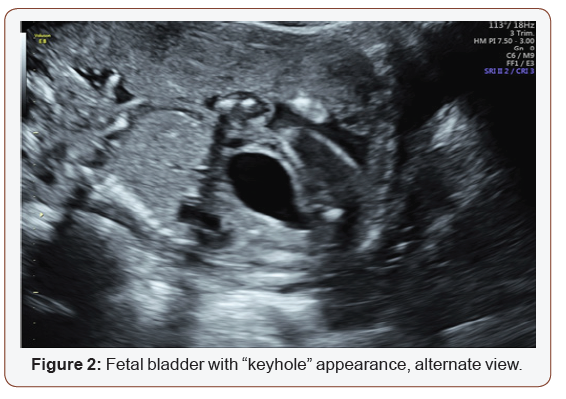

Fetal anatomy survey performed at 20 weeks gestation revealed multiple fetal anomalies, including bilateral cystic dilation of the pelvic and calyceal spaces, bilateral hydronephrosis, an enlarged urinary bladder, and oligohydramnios. Several sonographic images suggested a dilated posterior urethra, demonstrated by the pathognomonic “keyhole appearance”. PUV was suspected at this time and close follow-up was recommended. The patient was evaluated again at 22 weeks gestation, and a targeted fetal ultrasound revealed worsening oligohydramnios with persistent distention of the urinary system. These findings confirmed the suspicion of posterior urethral valve disorder.

The patient was counseled on the findings and expectations of this anomaly during the anatomy scan and genetic testing was offered. Amniocentesis showed elevated AFP (23.1 mcg/mL) and chromosomal analysis revealed a 46XY fetus. Additionally, the chromosomal micro assay exhibited a fetal chromosomal abnormality: arr [hg19] 16q24.2 (88, 059, 561-88, 647, 325) x 3. Approximately 588 kb interstitial gain of 16q24.2 was detected in this male fetus. This duplication included a segment of the BANP gene (OMIM: 611564), complete copies of the genes ZNF469 (612078), ZFPM1 (601950) and MIR5189, plus a segment of the ZC3H18 gene (not annotated in OMIM) (Figures 1-5).